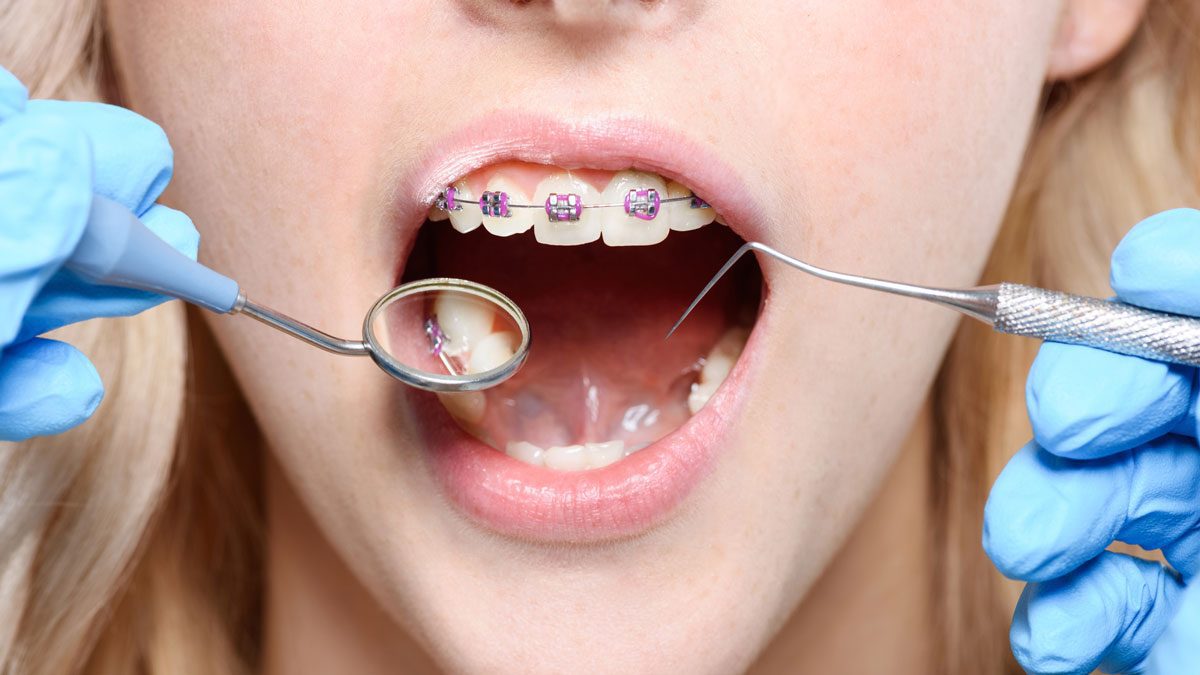

How do dentists put on braces?

Braces are one of the most common dental procedures. Most dental offices can install them, and if you want to straighten your teeth they’re one of the time-honored ways to do that. Are you aware of how they work?

Braces are one of the most common dental procedures. Most dental offices can install them, and if you want to straighten your teeth they’re one of the time-honored ways to do that. Are you aware of how they work?